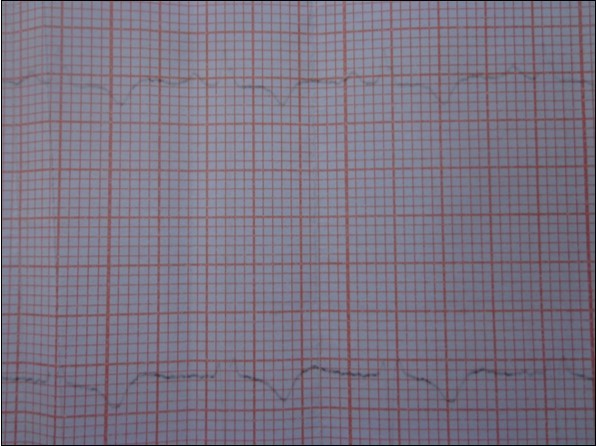

The chest X-ray was without abnormalities. The electrocardiogram demonstrated epicardial ischemia in the infero-lateral territory without other abnormalities (Figure 1). The cardiac troponin I was slightly elevated (32ng/l, N<19ng/l). Subsequent controls after 30min, 60min, and 180min did not show significant variations.

Figure 1.Electrocardiogram: epicardial ischemia in the infero-lateral territory.

On the electrocardiogram, signs of myocardial necrosis may be due to thinning of the myocardial layers surrounding the cyst, or secondary to obstruction of the coronary vessels by daughter vesicles 11; a true necrotic Q wave can also be seen 11, 23.

In our observation, the absence of cardiovascular risk factors, the absence of underlying diseases, the young age, the normalcy of coronary angiography, the concordance of territories between epicardial ischemia and HC, as well as the normalization of the electrocardiogram and troponin Ic after the surgical cure of the cyst makes it possible to advance a direct link of causality between this tumor and the myocardial ischemia.